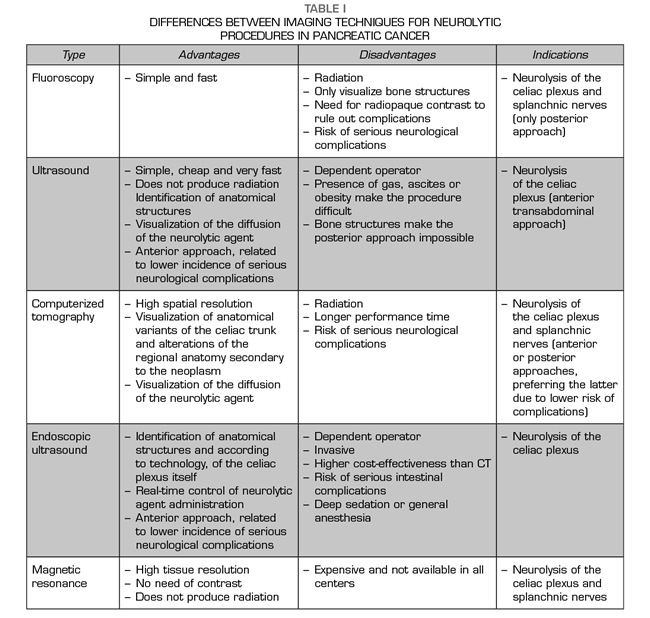

Each imaging technique has advantages, disadvantages and indications, which are summarized in Table I.

According to the percutaneous approach